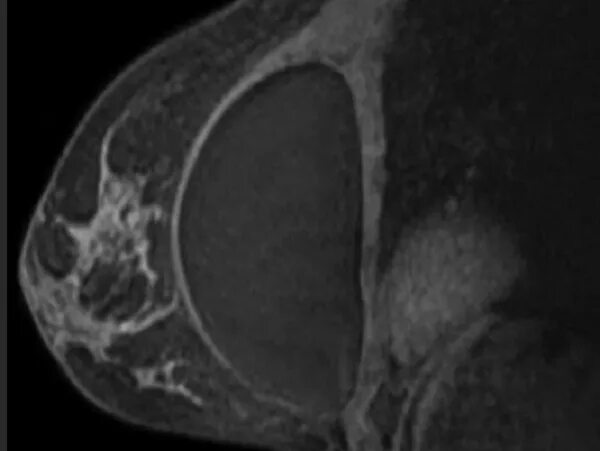

Как проводится мрт молочной железы